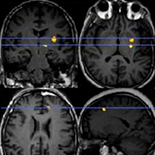

OCD patients had higher Obsessive Beliefs Questionnaire (OBQ-87) subscale scores than subjects in non-resistant and resistant groups. A significant difference was found between non-resistant and resistant OCD patients in R-Scale and I-Scale. A significant decrease in FA was found in left dorsal frontal gyrus and left inferior parietal lobule in the non-resistant group as compared to the control group. FA also decreased significantly in left anterior cingulate cortex, putamen, and nucleus accumbens in the resistant group as compared to the control group. There was a significant decrease in FA in nucleus accumbens in the resistant group as compared to the non-resistant group. Reduced FA in left nucleus accumbens was negatively associated with OBQ-87 factor R and I and the total Yale-Brown Obsessive-Compulsive Scale (Y-BOCS).